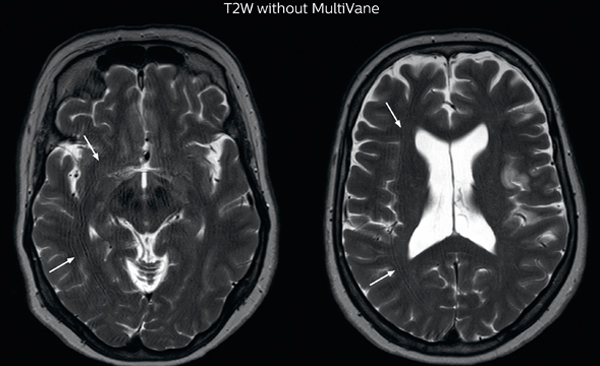

The images made with MultiVane XD show significant reduction in motion artifact compared to the T2-weighted images without MultiVane below them. Scanned on Ingenia 3.0T

“Motion artifacts can obscure subtle findings, make image interpretation more difficult and decrease diagnosis confidence. For example, when imaging the cerebellum or brain stem, or when looking for subtle multiple sclerosis (MS) lesions, motion can be problematic,” says Dr Nickerson. MultiVane XD motion-free imaging delivers diagnostic images even in the case of severe patient motion. A more relevant patient group is one with typical small artifacts related to moderate motion like an occasional cough. The absence of those artefacts brings forth better day-to-day diagnostic confidence. MultiVane XD works in multiple orientations and for various contrasts, such as T1-weighted, T2 weighted and FLAIR. Trevor Andrews, PhD, explains that the team compared motion artifacts seen in the brain with MultiVane XD and with T2-weighted TSE. “In nine out of the ten datasets in our studywe saw clear improvementswith MultiVane XD, while in the tenth dataset image qualitywas comparable. The MultiVane XD sequence is now used in the majority of patients that present at UVM for brain MRI.”

“We saw MultiVane XD provide remarkable improvement, not only for artifacts caused by patient motion, but also for the extent of pulsation artifacts in the basal cisterns. Based on these results, we have added the MultiVane XD sequence to our brain studies,” says Dr. Nickerson. “MultiVane XD is especially useful when imaging patients with diseases that cause white matter changes on T2-weighted images, such as MS, small vessel disease, vasculitis and sarcoidosis,” says Dr. Nickerson. “Many of these are only visible on T2-weighted or FLAIR images, and sometimes aren’t even seen with FLAIR images. However, when using MultiVane XD and we don’t see any motion on the rest of the scan, but still do see a signal abnormality, we can probably attribute that to a real disease process, rather than an artifact.”